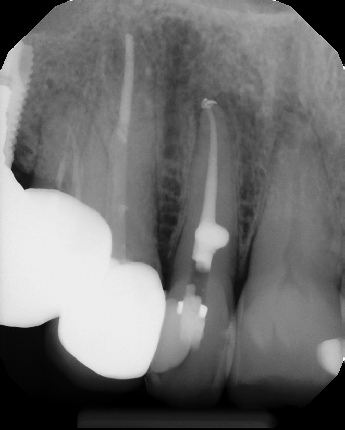

COMPLICATED ANATOMY LARGE LESIONS CALCIFIED CANALS PERFORATION / RESORPTION SEPARATED INSTRUMENTS SURGICAL CASES RETREATMENT / pOST REMOVAL OPEN APICES ACCESS THRU CROWNS Root Canal Case Portfolio